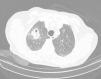

An 82-years-old male was referred to the Pulmonology Department due to right thoracic pain and episode of haemoptysis. A computed tomography (CT) scan showed a solitary pulmonary lesion in the upper right lobe (Fig. 1), with 18-fludeoxyglucose uptake on positron emission tomography-computed tomography.

Radiological patterns may contribute to definite diagnosis with upper lobe pleural thickening and subpleural fibrosis and less/absent lower lobe involvement on high resolution computed tomography (HRCT),2,3 without reference to defined nodular pattern as seen in this case.